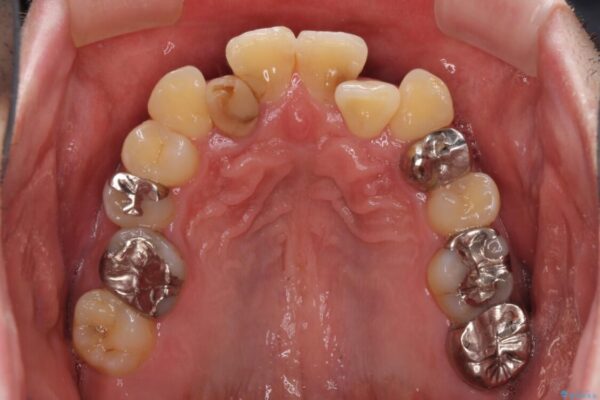

奥歯の痛みと前歯のデコボコを気にして来院された患者様です。

左右下顎の大臼歯は、ともに歯根が破折しており、抜歯が必要な状態でした。

放置したことで炎症による骨吸収が顕著であるため、骨造成を併用してインプラント埋入を行うこととしました。

咬み合わせは受け口傾向であり、上顎前歯の叢生が顕著であったことから、第1小臼歯抜歯による矯正治療も検討しましたが、下顎大臼歯を左右ともに抜歯するため、非抜歯による矯正治療を行うこととしました。

治療前